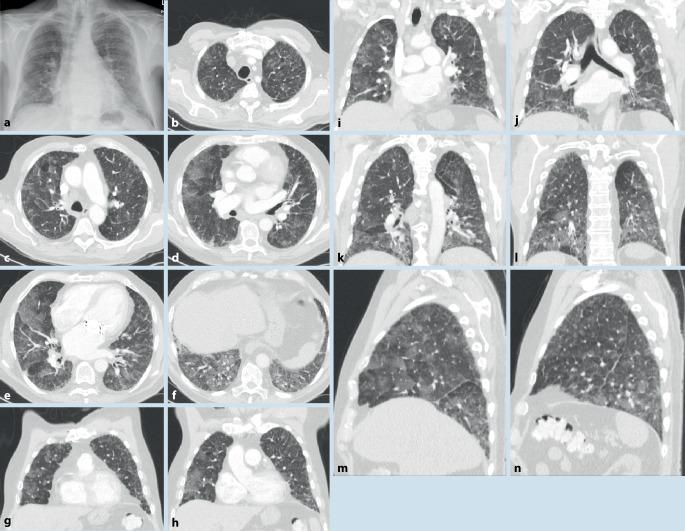

Rheumatic diseases frequently present with pulmonary involvement. All anatomic structures of the lungs can be affected. Interstitial lung diseases are characterized by a system of patterns evident in high-resolution computed tomography (HR-CT) scanning of the lungs. The HR-CT pattern can differ between rheumatic diseases.

风湿性疾病常伴有肺部受累。肺的所有解剖结构均可受到影响。间质性肺疾病的特征是在肺部高分辨率计算机断层扫描(HR-CT)中可见一系列明显的影像表现。不同风湿性疾病的HR-CT影像表现可能有所不同。

肺部受累很常见且与预后相关。肺部受累的概述显示,炎性风湿性疾病的受累解剖结构以及间质性疾病的影像表现具有高度变异性。提供了主要诊断结果的概要。

结论

此处提及的每种风湿性疾病都可能与肺部受累相关。因此,在首次诊断以及随访期间,必须进行系统的诊断评估。除了临床症状和肺功能外,肺部HR-CT对诊断起决定性作用。